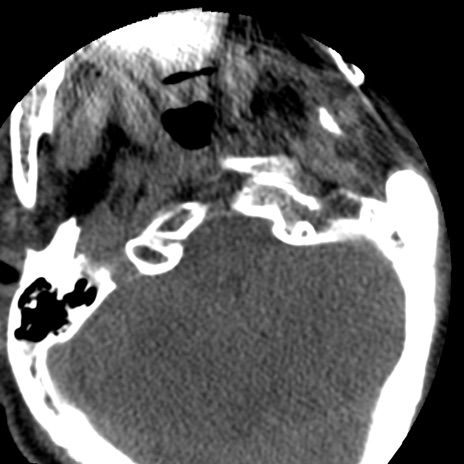

冠状断像

矢状断像